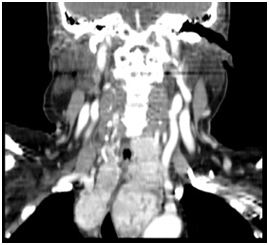

Figure 1 MRI demonstrating goiter extending under aortic arch.

Figure 4 Goiter extending under aortic arch (coronal view).